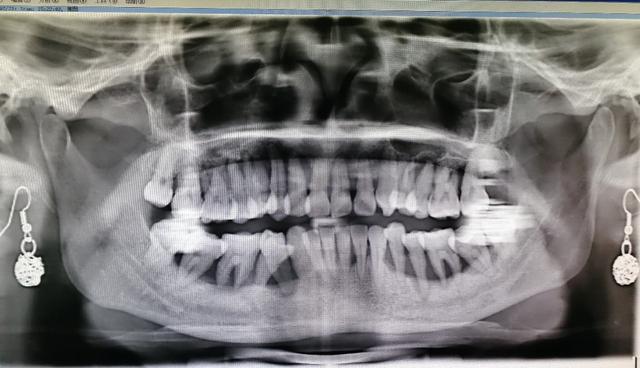

前几天一个30岁左右的女性顾客来到我的诊所,她是一位一岁孩子的妈妈,在整个孕期和哺乳期期间,觉得自己的牙齿不舒服出现了松动的情况,现在孩子一岁了,打算在上班之前先处理一下牙齿的问题

一看她的牙齿,我就知道大事不妙,给她拍完x光片以后,我数了一下,她大概只能留下4~6个牙齿……

她没想到问题那么严重,当场就懵了,接着泪流满面……

这就是我们口腔当中最常见的一种疾病__牙周炎,但是像她这个年龄就那么严重的还是比较少见的,多见于45岁以上的人群,严重者可导致整口牙齿都掉光,也是我国中老年人群当中,牙齿脱落的最主要的原因之一